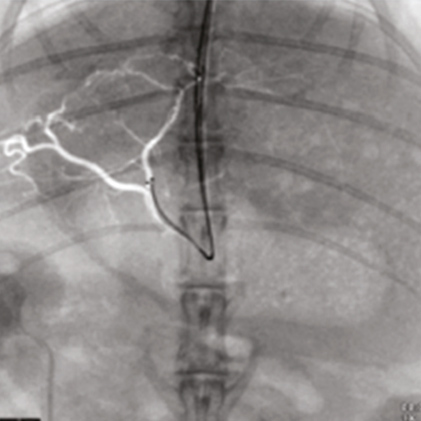

DSA(Digital Subtraction Angiography) helps various clinical diagnosis and procedures through the vessel image information after injecting contrast medium.

Providing excellent diagnostic images through accumulated experience.